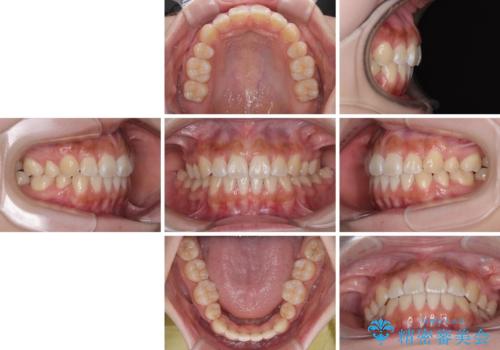

口元の印象が劇的に解消され、気にしていたガミースマイルも図らずも改善することができました。

上下前歯が嘴のように前方に突出しており、唇が閉じにくい状態であったため、上下左右の第一小臼歯4本を抜歯して、口元の突出感を改善することとしました。